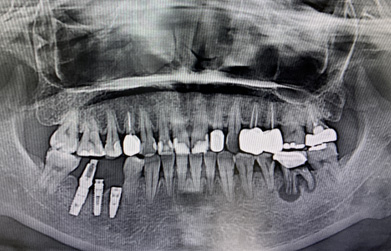

一口潔白整齊的牙齒,可以增加你的自信,讓你盡情展露笑容。但是很多人因?yàn)楦鞣N原因,從而缺失了自己的牙齒。嚴(yán)重影響的形象美觀及正常咀嚼功能。不過(guò)現(xiàn)在種植牙是非常熱門(mén)的項(xiàng)目,效果也是很不錯(cuò)的。 種植